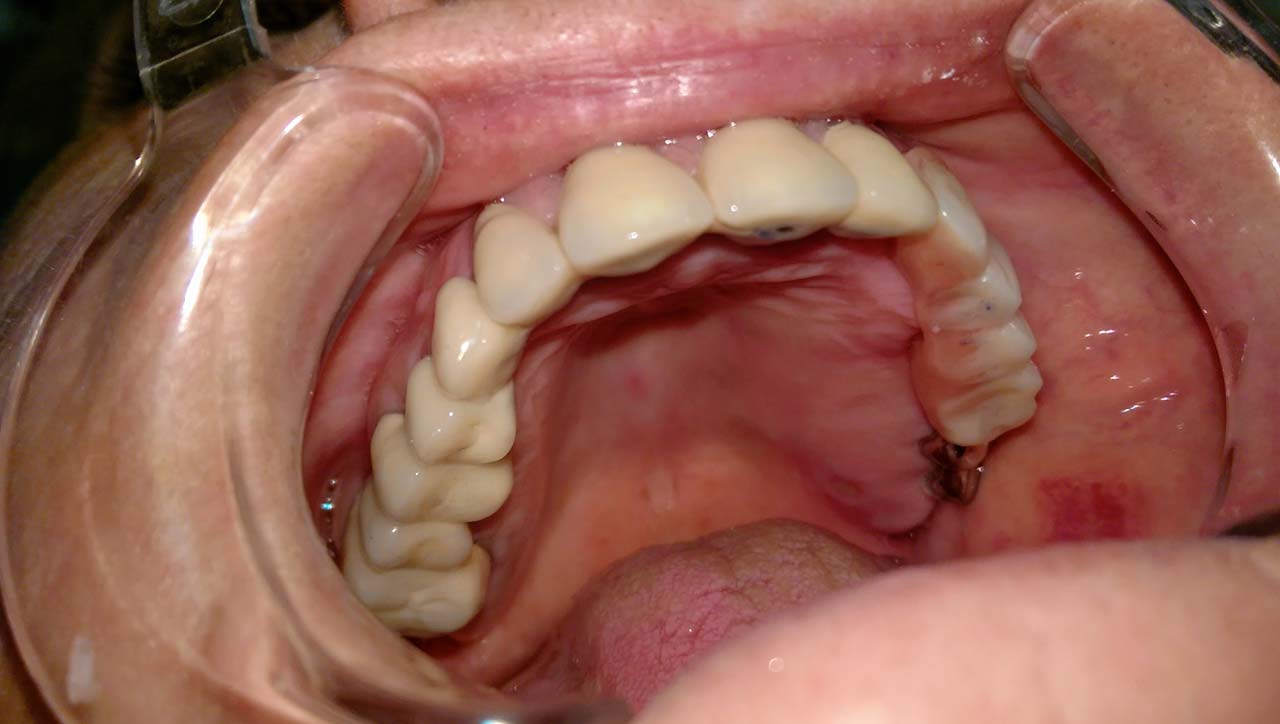

2 nap alatt varázsoltuk ezt a szép esztétikus alsó, felső körhídat implantátumokkal megtámasztva a korábban elhanyagolt szájba. Az 1. nap 26 fogat távolítottunk el, mert annyira rossz állapotban voltak, és rögtön azonnal terhelhető IHDE svájci implantátumokat raktunk be, fentre 8, lentre 6 darabot. A sebeket összevarrtuk és intraorális szkennerrel digitális lenyomatot vettünk. 2 nap múlva pedig beragasztottuk a kész PMMA műanyag körhidakat. Dr. Kelemen Péter és a Symbion Fogtechnika munkája.

Teljes fogatlanság helyreállítása 2 nap alatt azonnal terhelhető svájci IHDE implantátumokkal és PMMA műanyag hidakkal. Intraorális szkennerrel vettünk lenyomatot az implantáció után, és erre a digitális mintára készítette el a fogtechnika a hidak digitális tervezését, majd faragta ki műanyagból. Ezt a gyors munkát az azonnal terhelhető implantátumok és a digitális lenyomat, tervezés segítségével tudtuk megcsinálni mindössze 2 nap alatt. Dr. Kelemen Péter és a Symbion Fogtechnika munkája.